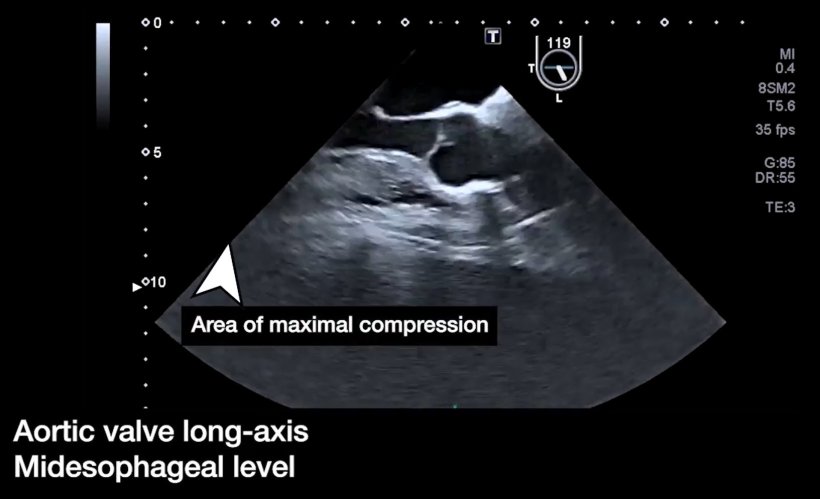

Every year, 3.8 million people suffer out-of-hospital cardiac arrests (OHCA). While CPR is the ultimate lifeline, survival rates remain suboptimal. Current "one-size-fits-all" chest compression guidelines lack strong clinical evidence, prompting researchers to challenge the status quo. Scientists conducted the world's first randomized clinical trial comparing conventional CPR with transesophageal echocardiography (TEE)-guided CPR. By using real-time imaging to precisely target the left ventricle and avoid the aortic valve, the team aimed to optimize every compression.